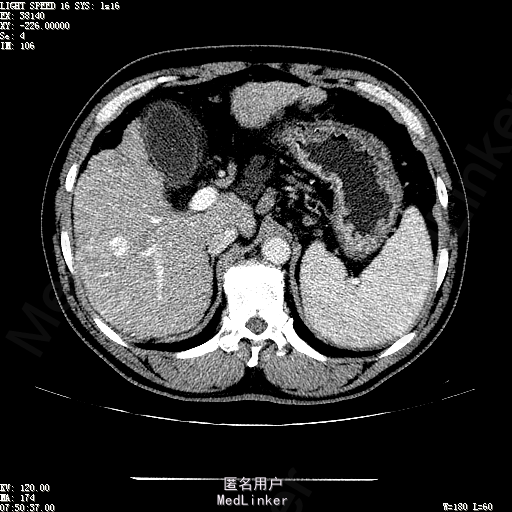

主诉:肝癌TACE治疗后36天 病史:患者两年前体检发现丙型肝炎病毒标志物阳性,于当地医院就诊诊断为"丙肝肝硬化",口服药物治疗,具体用药不详。定期复查肝功及肝脏影像学检查,2月前于医大二院行肝脏增强磁共振检查发现肝S6段动脉期增强结节,36天前在我院行DSA肝动脉造影明确"原发性肝癌"诊断并行"TACE"治疗,术后恢复良好,现患者为进一步行肝癌局部消融治疗来诊。

诊断:1、丙肝肝硬化 代偿期;2、原发性肝癌 S5段、S6段 该患诊断明确,既往曾行TACE治疗肝癌,S5段、S6段近右肾上极2处碘油沉积明确,S5段者较大,约2.31cm。超声显示清晰,为防止癌灶复发,适合行射频消融治疗。